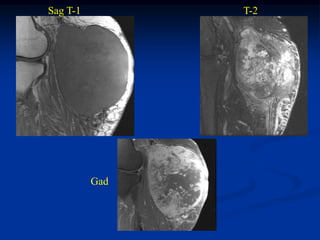

Case #257.1              Sag T-1

48 year male with

recurrent lump on

plantar aspect of foot

recurrent from surgery

17 years ago

T-2                  Gad

Axial T-1    T-2

Gad